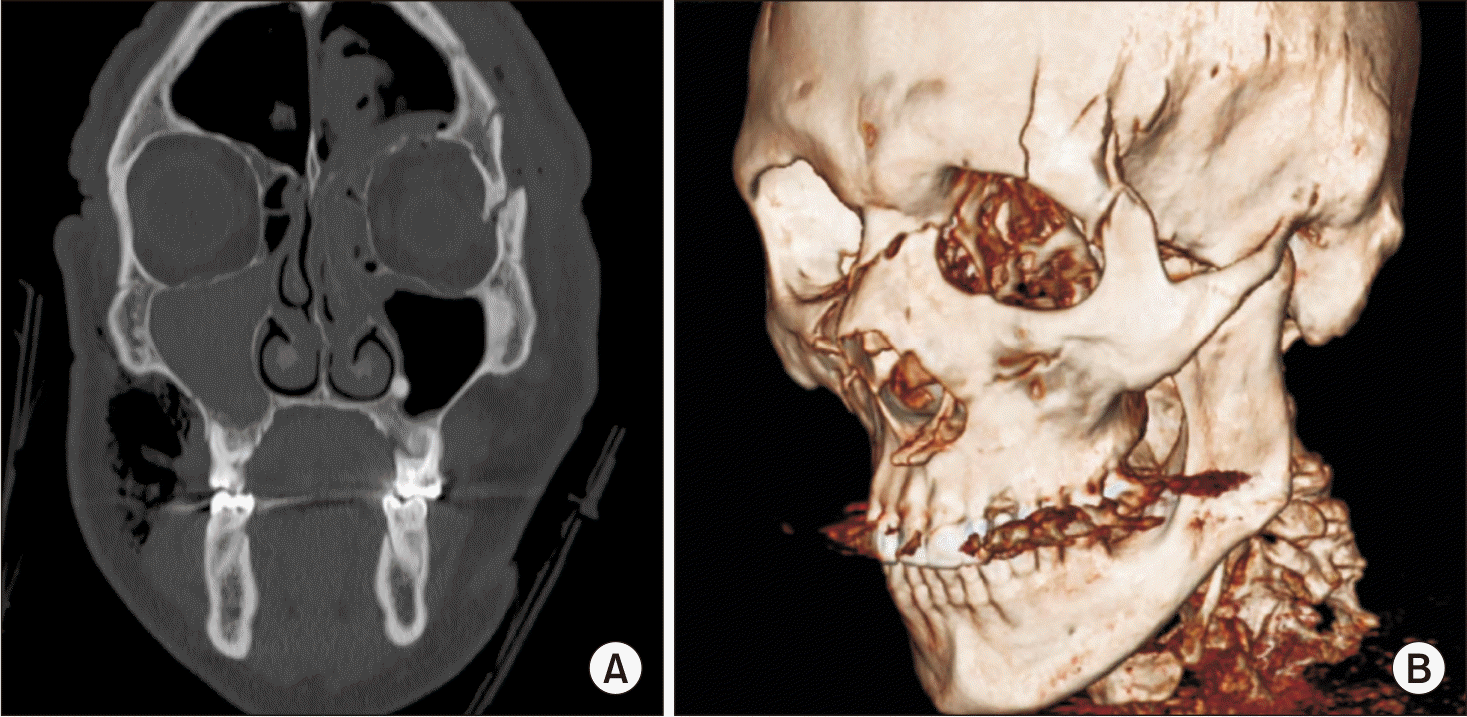

A 69 year-old male patient without comorbidities was admitted to the regional hospital of Rancagua with a diagnosis of a left fronto-orbito-zygomatic fracture.(Fig. 1) Due to the complexity of the fracture, conservative treatment was not feasible, and the patient underwent surgical intervention under general anesthesia. The chosen approach was an upper eyelid incision combined with a lateral canthotomy (Fig. 2), followed by reduction and osteosynthesis of the lateral orbital wall and part of the frontal bone.

Fig. 1

Preoperative (A) computed tomography scan and (B) three-dimensional reconstruction showing left fronto-orbital-zygomatic fracture with intermediate segment.